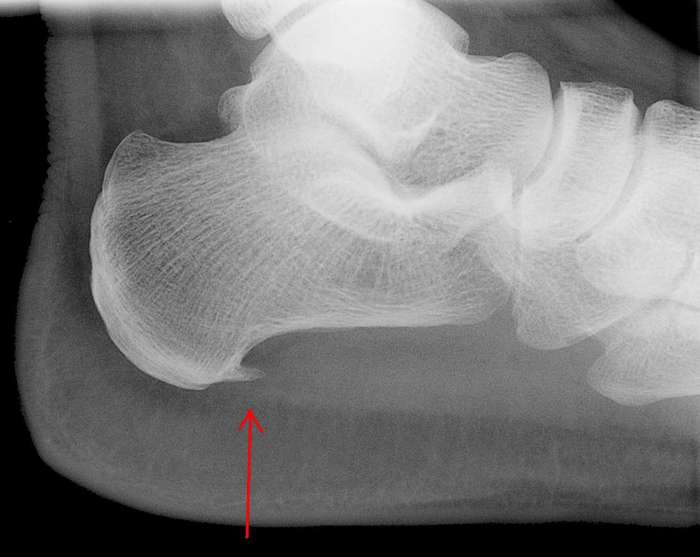

Heel Bone Spur Photograph by Zephyr/science Photo Library Pixels What Is A Spur On The Bone What is a bone spur? Enthesophytes form in the tendon or ligament. It is also called an osteophyte. The most common cause of bone spurs on feet is. Bone spurs commonly grow on top of the foot, on the toe, and on the back of the heel where the achilles tendon connects to the heel bone. Bone spurs, also called. What Is A Spur On The Bone.